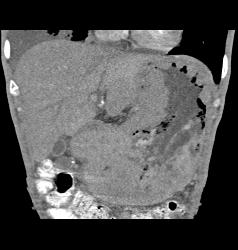

Gastric Lymphoma With Nodes and Ulceration